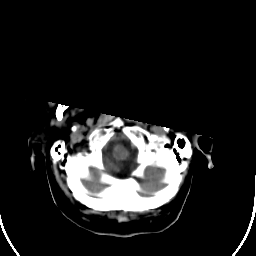

Stroke CT #1 -- Slice #1

[Home][Help][Clinical] Slice 1